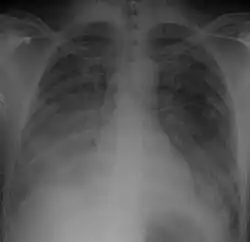

Chest Xray of a 40 yr old male in acute respiratory distress syndrome as a complication of murine typhus | |